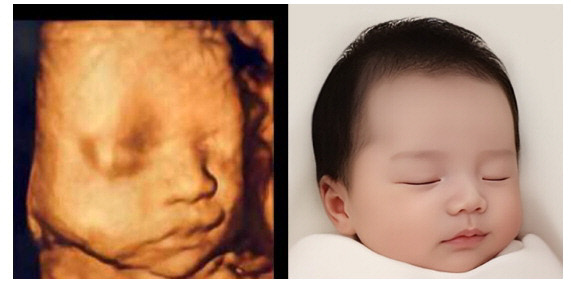

![]() 이미지생성 AI프로그램으로 태아의 입체초음파 이미지<왼쪽>를 이용해 생후 50일 아기 모습<오른쪽>을 예측·제공한다. |

이미지 생성 인공지능(AI) 업체인 알레시오㈜의 ‘베이비페이스’는 태아의 입체초음파 이미지를 이용해 생후 50일 아기 모습을 예측해 준다. 독자적인 AI 기술을 통해 흐릿하고 가려진 입체초음파 이미지에서 아기 얼굴 특징을 추출하는데, 미래에 태어날 아기 얼굴 사진을 미리 산모에게 제공하는 신기술이다.

또 동영상 생성 AI 기술을 탑재한 ‘베이비페이스 4D’(동영상)는 베이비 페이스에서 예측한 아기 얼굴을 활용해 귀여운 표정 등을 담은 실제 살아있는 듯한 아기 모습을 마주할 수 있다. 광주에 거주하는 시민은 3만5000원짜리 해당 프로그램을 1회 3500원에 이용할 수 있다.